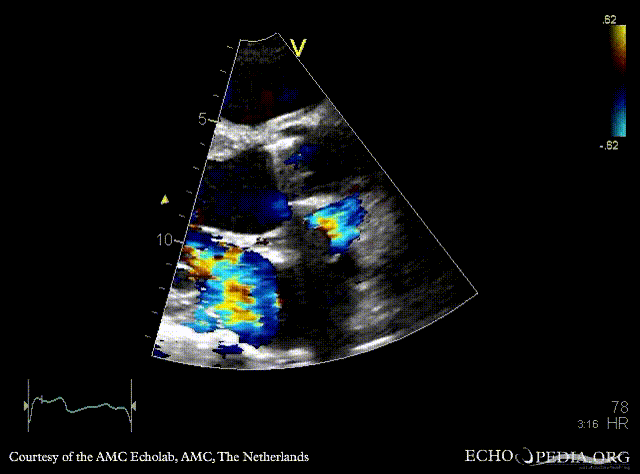

E00846.gif E00847.gif

PSAX: abscess of aortic valve prosthesis A4CH with Color Doppler: flow from abscess into the left atrium, severe mitral regurgitation